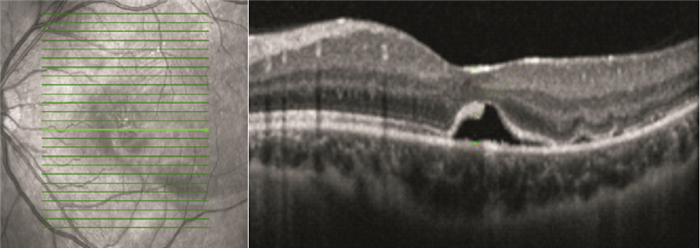

OCT檢查發現,手術后視網膜下液吸收時間1~13個月,平均視網膜下液吸收時間(7.82±3.52)個月。手術后12個月,42只眼中,視網膜下液吸收37只眼,占88.1%;視網膜下液殘留5只眼,占11.9%。視網膜下液吸收37只眼中,視網膜微結構正常15只眼;神經上皮層黃斑囊樣水腫5只眼(圖 1);光感受器內外節連接(IS/OS)斷裂12只眼;IS/OS和外界膜(ELM)斷裂5只眼(圖 2)。

患眼OCT像。IS/OS聯合ELM斷裂

患眼OCT像。IS/OS聯合ELM斷裂

OCT檢查發現,手術后視網膜下液吸收時間1~13個月,平均視網膜下液吸收時間(7.82±3.52)個月。手術后12個月,42只眼中,視網膜下液吸收37只眼,占88.1%;視網膜下液殘留5只眼,占11.9%。視網膜下液吸收37只眼中,視網膜微結構正常15只眼;神經上皮層黃斑囊樣水腫5只眼(圖 1);光感受器內外節連接(IS/OS)斷裂12只眼;IS/OS和外界膜(ELM)斷裂5只眼(圖 2)。

患眼OCT像。IS/OS聯合ELM斷裂

患眼OCT像。IS/OS聯合ELM斷裂

光感受器細胞IS/OS連續及ELM完整,是實現正常視覺的重要條件[8]。惠延年[9]認為視網膜脫離復位后,隨著IS/OS修復,視力逐漸恢復。而當IS/OS聯合ELM受損時則預示著這種損害擴展到細胞體及Müller細胞。因ELM較IS/OS更靠近細胞核,ELM受損代表光感受器細胞損傷加重,并且已有研究表明,單純IS/OS斷裂可以自行恢復,而聯合ELM受損后,IS/OS不能恢復[10, 11],表明ELM損傷對在IS/OS損傷修復中的作用,并且側面反映出ELM損傷對IS/OS的影響。本研究IS/OS斷裂12只眼中,聯合ELM破壞5只眼,印證了Delolme等[12]觀察的IS/OS受損多聯合ELM損傷的觀點。